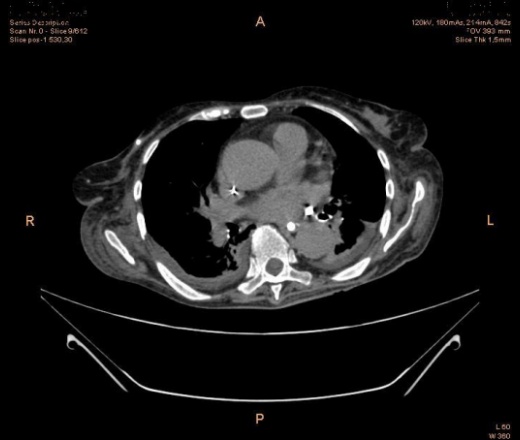

Нужна ваша помощь.Больная 76 лет.2 нед. назад перенесла операацию ЖКБ.Гангренозный холецистит, перитонит, сепсис.Переведен нашу больницу с диагнозом : ПХЭС.Мех .желтуха.

Больная ослабленная гемогл 76,0 .лейкоцит 15,0.эрит-2,8.СОЭ15,0.Мы хотели сделать в\в контрастир.вены лопались подкожно ушел контраст .Пытались ручную контрастир вот что получилось.

МПР не получается почему -то я извиняюсь заранее.Холедох не прослеживается .

Тогда DICOM , вероятно, поможет спасти гигантов мысли. Иначе толщину стенки 12-перстной мне не объяснить, как и воздух на месте ложа желчного пузыря. Где и что сшили, какой анастомоз... если к дайкому приложить протокол операции... вообще было бы супер-пупер. Внутрипеченочные желчные пути правой доли расширены, отсюда бы и плясать. Вроде 1 дренаж, в подпеченочном пространстве... Если его активно моют, то воздушка в ложе может из дренажа быть.

Анастомоза нет.Лапоротомия удаления ж.пузыря.Я думала правой доли печени очаг как множественные пиогенные абсцессы.Под печеночном простран. дренаж. А правом боковом канале и в малым тазу своб. жидкость.Вообще -то у нее стояло подключичка анестезиолги рек -ли контраситров через подключичку,т.к. вены слабые.Я отказалось (потому что мы всегда делаем в\в через локтевой)поставили локтевой катетер вены тонкие были скорость 2,5 мл.Можно ли проводить в\в контрастирование через подключичку?